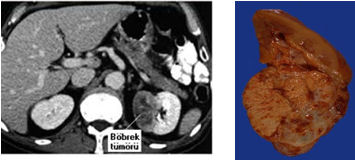

BİLGİSAYARLI TOMOGRAFİ (CT)

Hem böbrek pelvisi hem de üreterdeki kitleyi gösterebildiği gibi etraf dokulardaki metastazlarıda gösterebildiği için tercih edilmesi gereken bir tetkik yöntemidir.